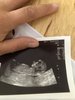

ja większy stres mam zawsze z niewiedzy i domysłów i na bieżąco nawet pomimo wewnętrznych oporów zmuszam się do badań. Myślę, że przykład dziewczyny może nie potwierdzać reguły więc ja bym sprawdziła właśnie USG, bo na dotyk lekarz też pewny być nie może co tam siedzi